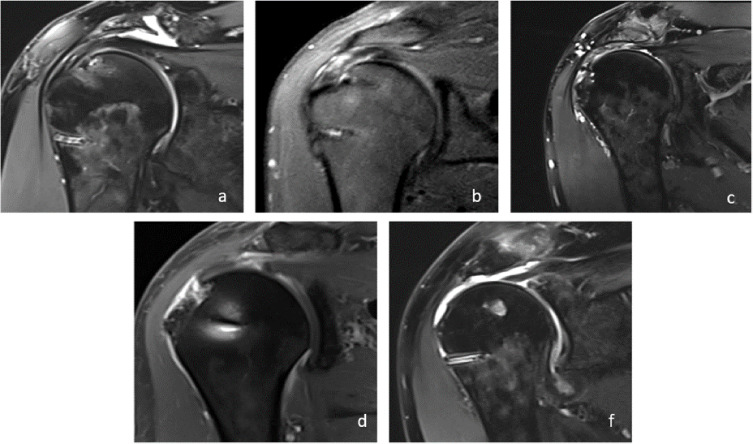

Failed Rotator Cuff Repair

Failure may present as pain, loss of function, or retear (20% incidence). Sugaya classification distinguishes:

- Type 2–3: Tendinopathy (no discontinuity)

- Type 4–5: Retear/discontinuity